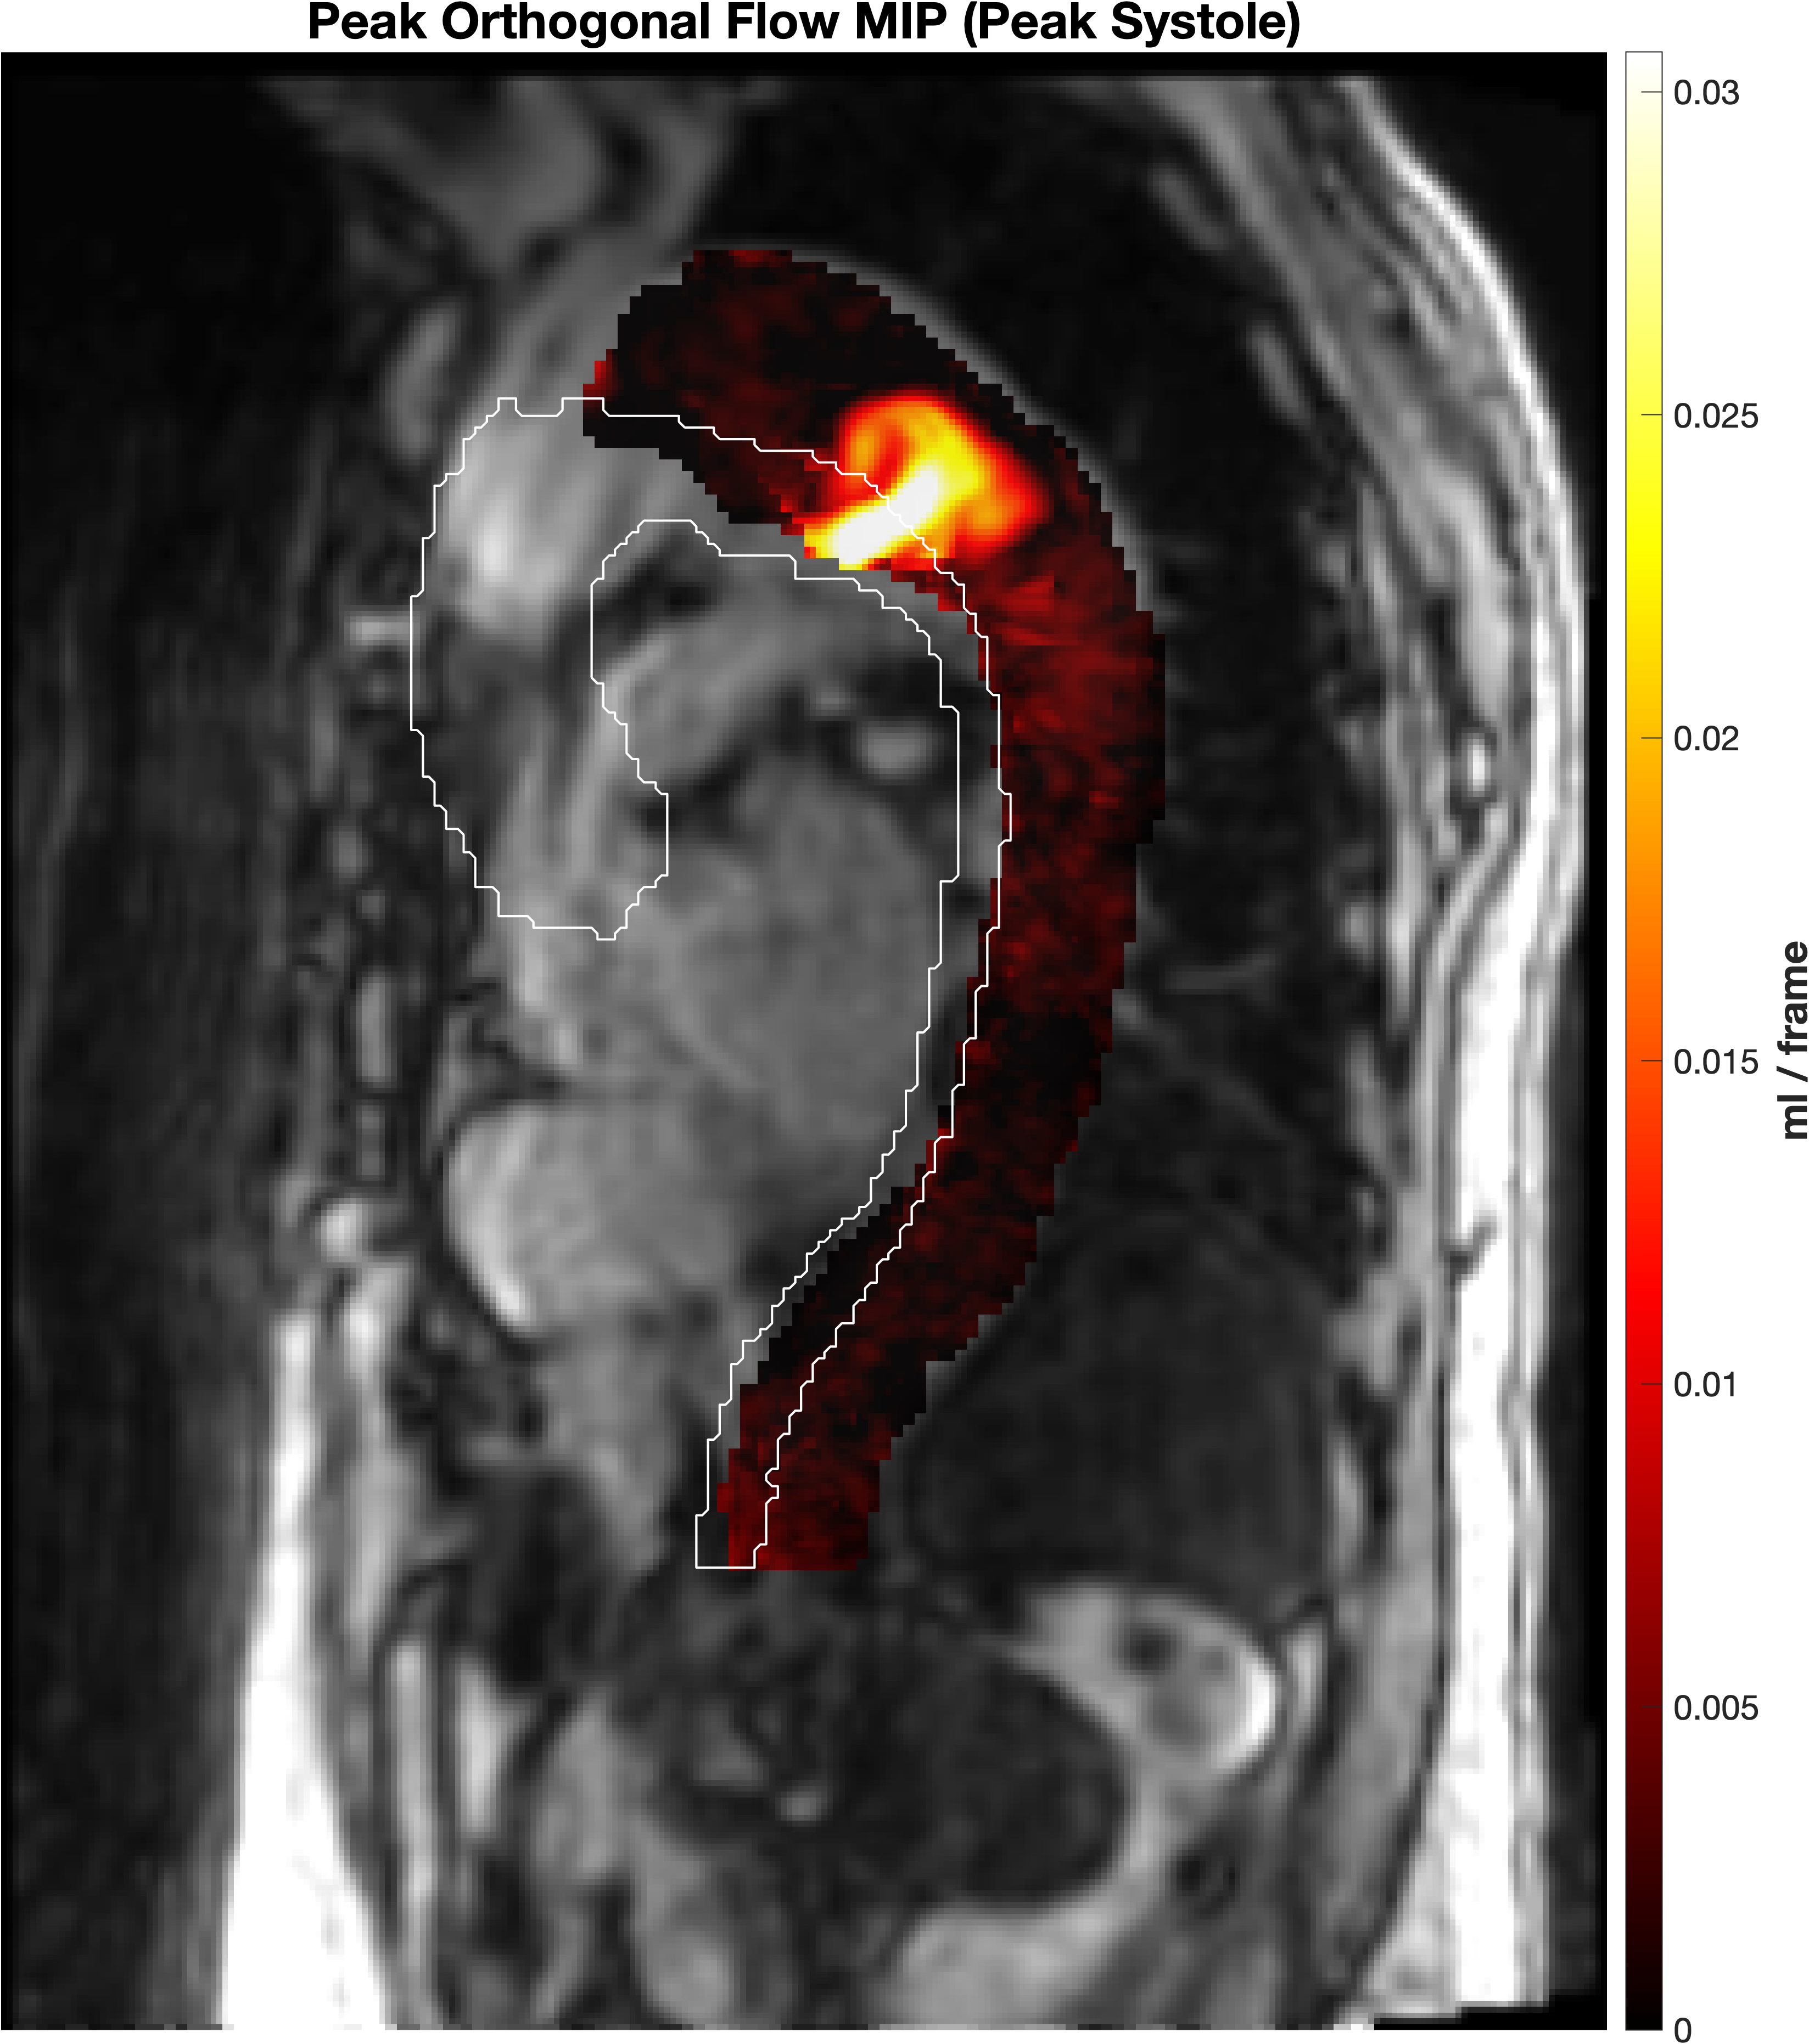

Peak orthogonal flow representation

Representative peak orthogonal-flow signal from a chronic dissection case. The detector operates on this distributed hemodynamic input.

The method converts this signal into discrete tear-level measurements.